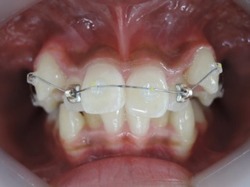

当院ではマルチループ(MEAW法)という上の写真で装着しているようなクネクネ曲がったワイヤーを使用して、上下の隙間を埋めていくことで歯並びを整えます。

出来るだけ見えにくい矯正装置(ブラケット)を上下顎に装着して歯並びを整えていきます。矯正装置を装着後3日から7日ぐらいまでの間は歯が動きだすために軽い痛みを感じることがあります。

次にMEAW(マルチループ)を利用する事で咬み合わせの高さや前歯の傾斜を整えていきます。

また、MEAW(マルチループ)はゴムを24時間使用する事で最大の効果を発揮することが出来ます。